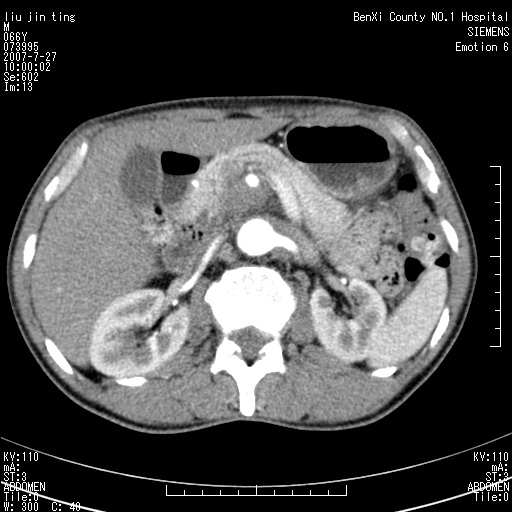

腹痛,背痛,无恶心呕吐,不黄,彩超示胰腺钩癌,ct扫描病灶平扫30-40hu,增强后动脉期40--60hu,静脉期50-68hu,真的是钩突上的么?您要试一试么?

动脉期

静脉期

沿着肠系膜上动脉呈匍匐性生长的软组织肿块,形态不规则,包绕肠系膜上动脉,呈明显强化,考虑来源于肠系膜的恶性肿瘤

沿着肠系膜上动脉呈匍匐性生长的软组织肿块,形态不规则,包绕肠系膜上动脉,呈轻-中度强化,考虑来源于肠系膜的恶性肿瘤。

钩突是正常的,只见腹膜后淋巴结的肿大,考虑淋巴瘤或转移可能。

支持!恶性纤维组织细胞瘤可能,与淋巴瘤及淋巴结转移鉴别(腹主动脉周围清晰,其他部位亦未见明显肿大淋巴结)。